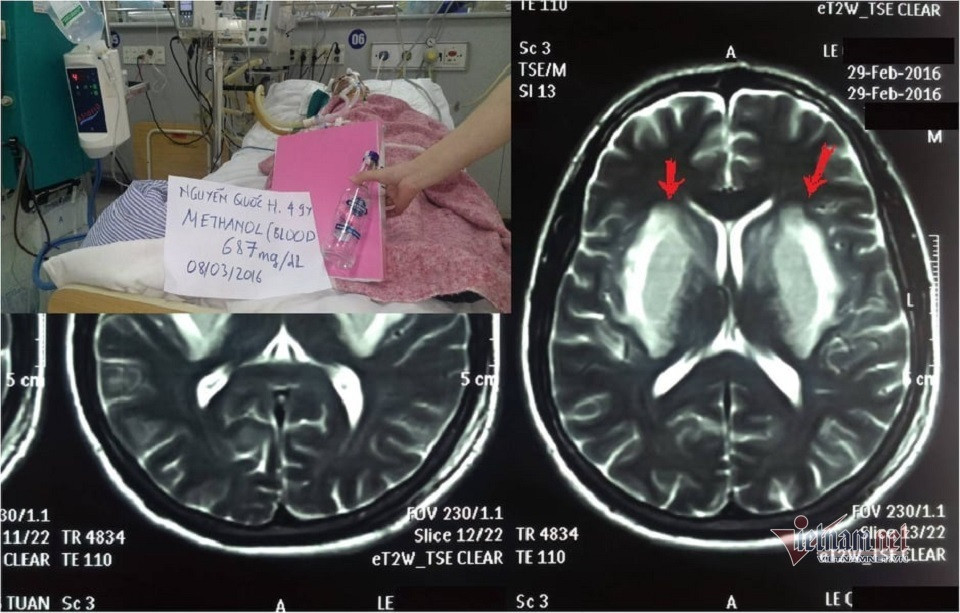

![]() |

| Hình ảnh não 1 bệnh nhân tổn thương nặng do uống phải cồn công nghiệp methanol: Ảnh: BS cung cấp |